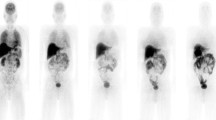

Figure 3A is the coronal PET image for a single female subject (no. 5) and demonstrates the typical biodistribution of [18F]FACT in the human body. The highest accumulations of this radioligand were observed in the gallbladder, liver, intestine and urinary bladder. For subject no. 1, [18F]FACT contained in the bile was excreted from the liver to the duodenum through the biliary tract (Figure 3B). The biodistribution pattern of [18F]FACT in human subjects showed a predominant hepatobiliary excretion, which is similar to what has been observed for other amyloid ligands, such as [11C]PIB, [18F]AV-45, [18F]GE067 and [18F]BAY94-9172 [7, 8, 10, 11].

Figure 4 shows the decay-corrected time-activity curve of the %ID for typical source organs (brain, liver, spleen, lung, kidney, heart content, heart wall, muscle, red marrow, small intestine contents, gallbladder, upper large intestine contents and urinary bladder) from the six volunteers and the mice experiments. A significant difference between the %ID from humans and mice was observed in the brain, liver, spleen, heart contents, red marrow and urinary bladder, and these differences propagated the different results regarding dose estimation. In human subjects, 18F uptake in the gallbladder contents and the intestines (Figure 4J,K,L) indicated larger individual variations in radioactivity uptake relative to other organs (e.g. the kidney as shown in Figure 4E). Radioactivity uptake in the upper large intestine showed propagation of both ligand kinetics and inter-subject variation from the gallbladder (Figure 4K,L). Scheinin et al. previously reported that inter-subject variation in ligand uptake ([11C]PIB) in the gallbladder may be due to the quality and quantity of post-injection food intake [7]. In the present study, the subjects drank water during the interval between the first and second PET scans. This may have been responsible for the increase in inter-subject variation regarding the gallbladder. Furthermore, because the gallbladder uptake in some subjects had declined or remained at a low level at the final time points, we assumed that there was only physical radioactive decay after the last PET scans. However, this assumption may have led to a conservative estimation of the absorbed dose.

Figure 5 presents typical brain PET images obtained using [18F]FACT at different time points with an acquisition time of 3 min (first, second and third emission) and 4 min (fourth emission). There was no significant retention of [18F]FACT in the brain, and this may have been because the subject was normal.